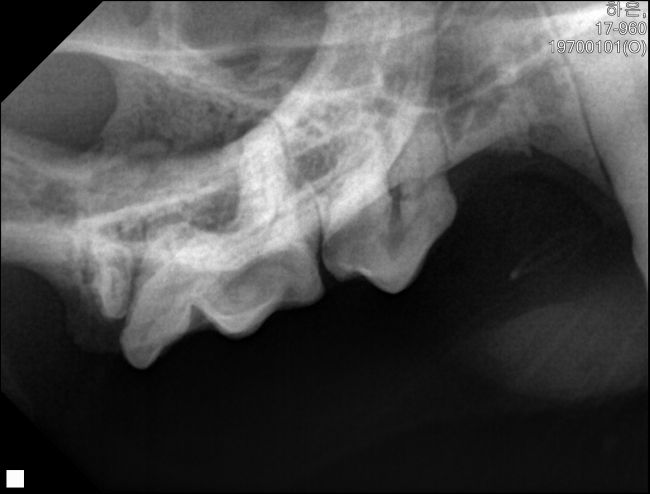

아래 앞니 엑스레이입니다.

오른쪽 아래옆 사진입니다.

오른쪽 위옆 사진입니다.